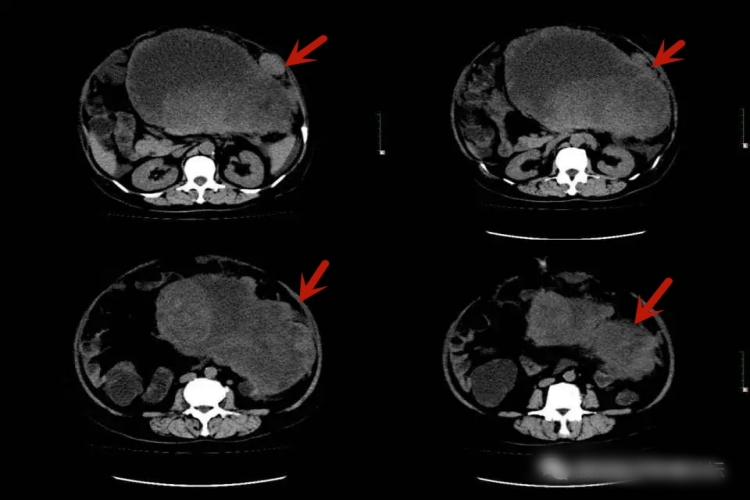

平滑肌肉瘤:平滑肌肉瘤多呈圆形、不规则形,大多有包膜而边界清楚,当存在周围侵犯时,可能表现为边界不清的肿块。